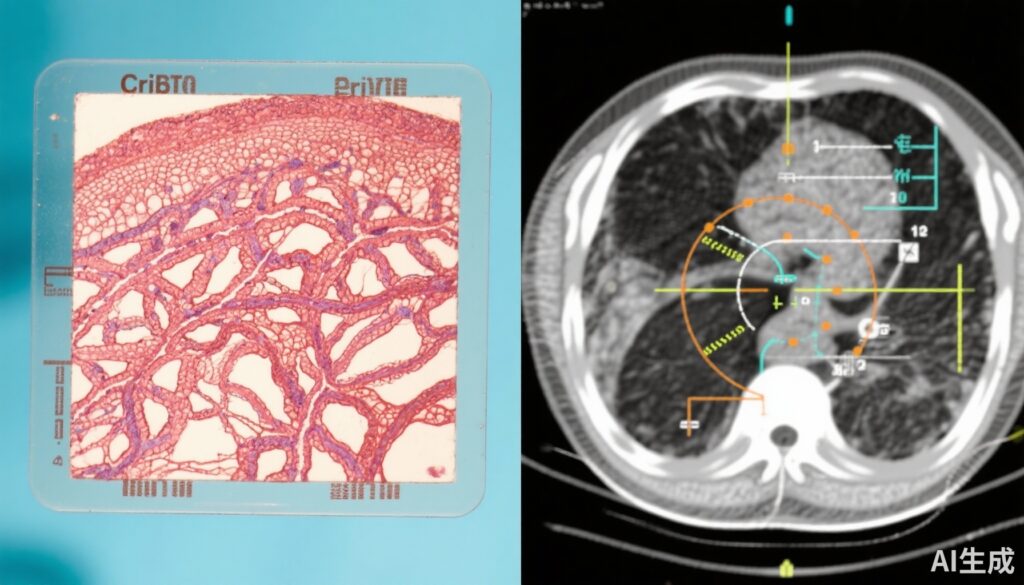

Ung thư tiền liệt tuyến vẫn là một trong những bệnh ác tính phổ biến nhất ở nam giới trên toàn thế giới. Các đặc điểm histopathologic, đặc biệt là cấu trúc cribriform—bao gồm ung thư cribriform xâm lấn và ung thư nội mao mạch—luôn được liên kết với hành vi khối u hung hãn và kết quả lâm sàng kém. Dù có ý nghĩa tiên lượng đã được biết, chiến lược quản lý tối ưu cho ung thư tiền liệt tuyến dương tính với cribriform vẫn chưa được xác định, đặc biệt do thiếu dữ liệu thử nghiệm lâm sàng ngẫu nhiên đánh giá nguy cơ di căn dài hạn liên quan đến tiểu loại này.

Thử nghiệm PROTECT là một thử nghiệm lâm sàng ngẫu nhiên giai đoạn 3 mang tính bước ngoặt được thực hiện từ 1999 đến 2009, tuyển dụng 1,643 nam giới mắc ung thư tiền liệt tuyến lâm sàng cục bộ. Người tham gia được ngẫu nhiên phân vào một trong ba chiến lược quản lý: theo dõi chủ động, cắt bỏ tiền liệt tuyến (phẫu thuật), hoặc xạ trị kết hợp liệu pháp tước androgen trước phẫu thuật (ADT). Phân tích phụ này xem xét lại các mẫu sinh thiết từ 712 người đàn ông có sẵn để đánh giá histopathologic tập trung. Bệnh nhân được phân loại là dương tính với cribriform nếu phát hiện ung thư cribriform xâm lấn và/hoặc ung thư nội mao mạch trong các slide sinh thiết chẩn đoán. Điểm cuối chính là tiến triển thành bệnh di căn, bao gồm di căn xương, nội tạng, hoặc hạch bạch huyết được xác nhận qua hình ảnh học hoặc nồng độ PSA vượt quá 100 ng/mL, trong vòng 15 năm. Cả phân tích theo nguyên tắc điều trị và phân tích theo giao thức đều được thực hiện, điều chỉnh các biến số quan trọng như tuổi, nồng độ PSA, điểm Gleason, và chỉ định điều trị.